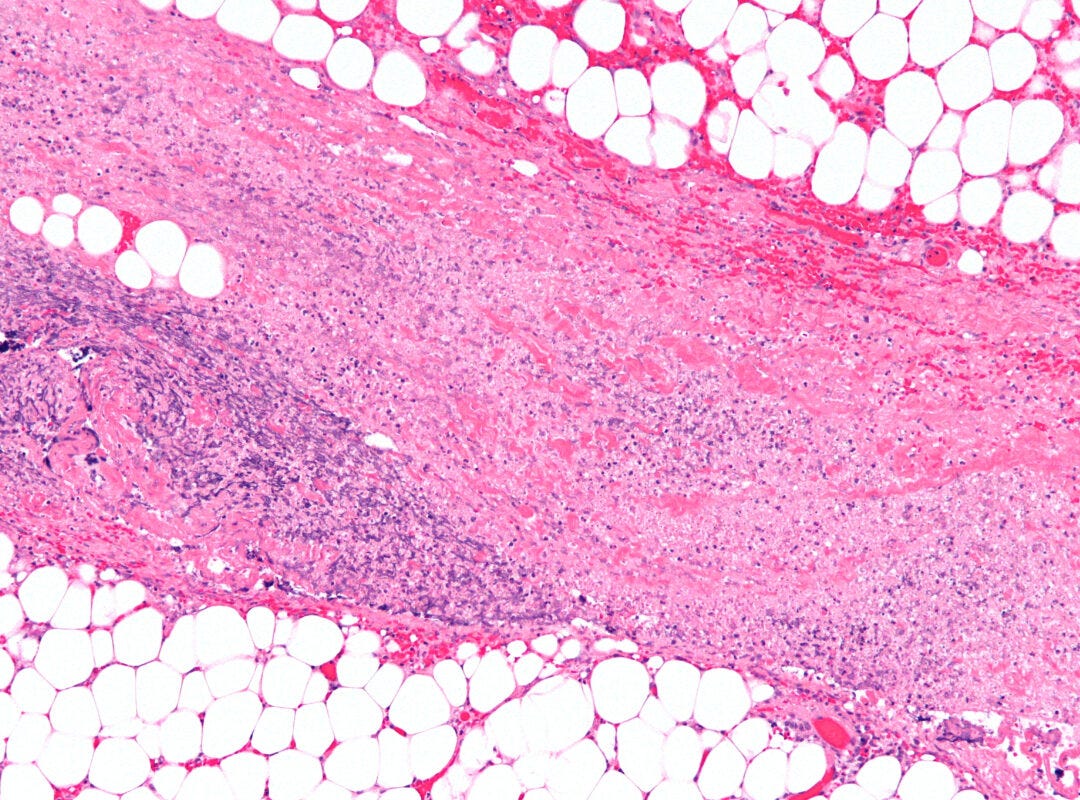

Today's new horror: necrotizing fasciitis of the vulva

Doctors in the U.K. report a rise in the number of cases of necrotizing fasciitis of the vulva.